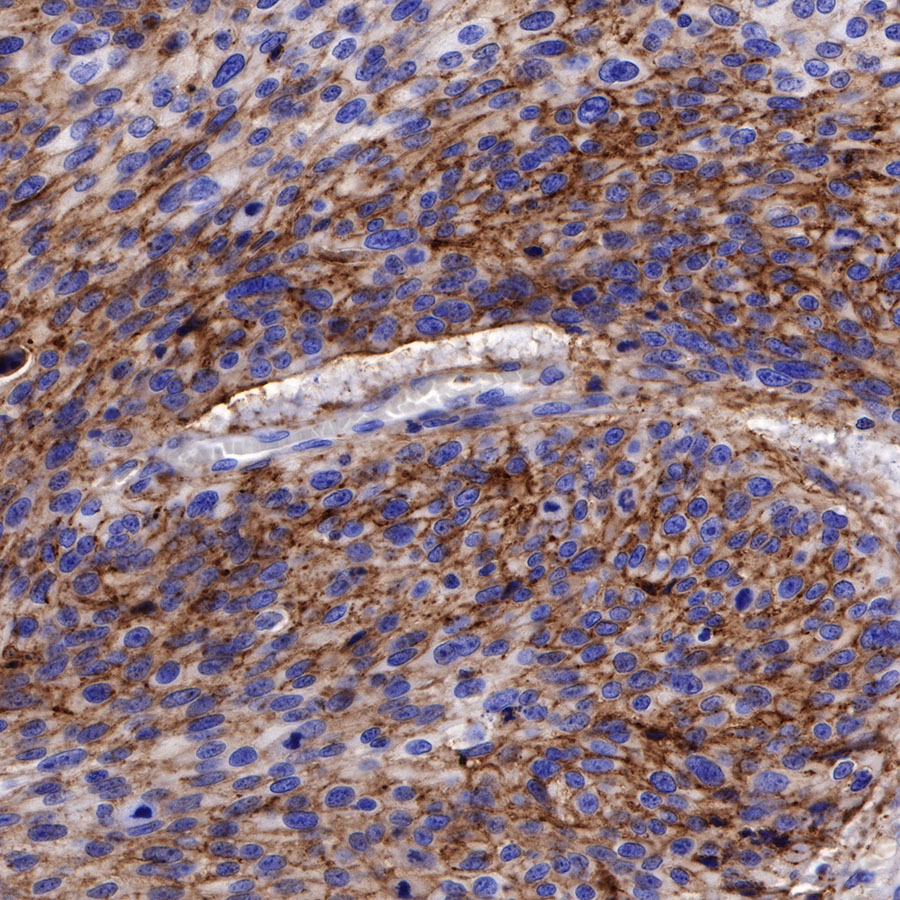

Immunohistochemistry

Syndecan-1 (CD138) is mostly restricted to epithelia, and bears heparan sulfate chains that are capable of interacting with a large array of polypeptides, including extracellular matrix components and potent mediators of proliferation, adhesion and migration. For this reason, it has been studied extensively with respect to carcinomas and tumor progression. Frequently, but not always, syndecan-1 levels decrease as tumor grade, stage and invasiveness and dedifferentiation increase. However, in some tumors, levels of syndecan-1 increase, but the characterization of its distribution is relevant. There can be loss of membrane staining, but acquisition of cytoplasmic and/or nuclear staining that is abnormal. Moreover, the appearance of syndecan-1 in the tumor stroma, either associated with its cellular component or the collagenous matrix, is nearly always a sign of poor prognosis [PMID: 33921767].